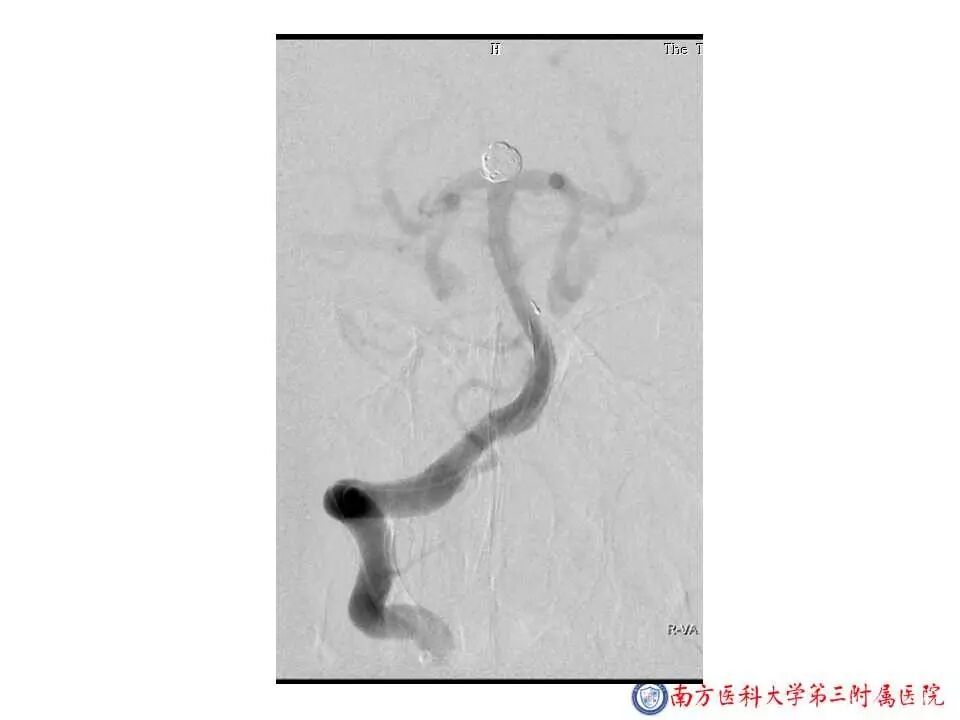

今天为大家分享的是“强生医疗CNV-神经介入专栏”第二十五期,由南方医科大学第三附属医院神经外科主任黄理金教授带来的“Enterprise支架辅助栓塞动脉瘤的优势”精彩讲课视频及PPT,欢迎观看。文章仅代表作者个人观点,如有不同见解,欢迎同道斧正!